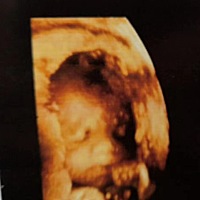

宝宝1天